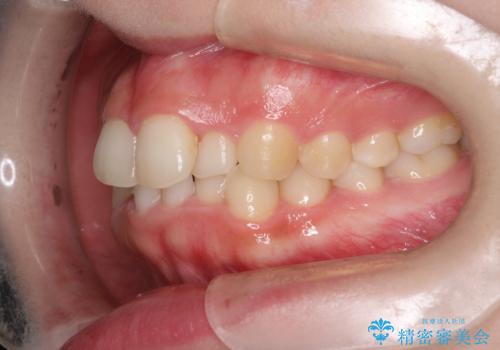

インビザラインでの前歯のガタガタの矯正

- 上下の前歯のがたつきを主訴に来院されました。

歯と歯の間をわずかに削りスペースを作り、インビザラインにて矯正治療を行うこととしました。

使用時間を守っていただけたので、スムーズに矯正を終了することができました。